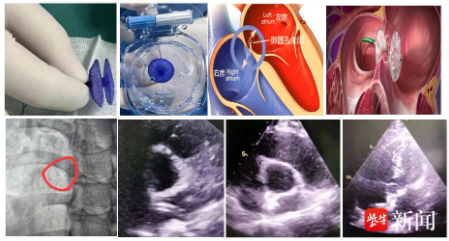

16日,院方介绍,该名年轻女性因长期反复头痛,在外院超声发泡试验(右心声学造影)强阳性,遂慕名至镇江瑞康医院心内科就诊。入院后经食道超声显示卵圆孔回声分离1.2 mm,明确诊断为“卵圆孔未闭(PFO)”,这正是导致她顽固性头痛的“元凶”之一。

手术在DSA和超声影像学双重定位下开展。生物可降解封堵器在超声下清晰可见,但在DSA下的显影有限,仅可见左右盘面及腰部分布的4个梅花样显影点,这就要求手术医师具备更高的操作技能和精细度。

术中,凭借DSA与超声影像的双重引导,术者犹如拥有“透视眼”和“慧眼”,通过精准输送到位后超声反复多切面验证,成功释放生物可降解封堵器。术中心脏彩超显示封堵器位置良好,固定牢固,无残余分流。